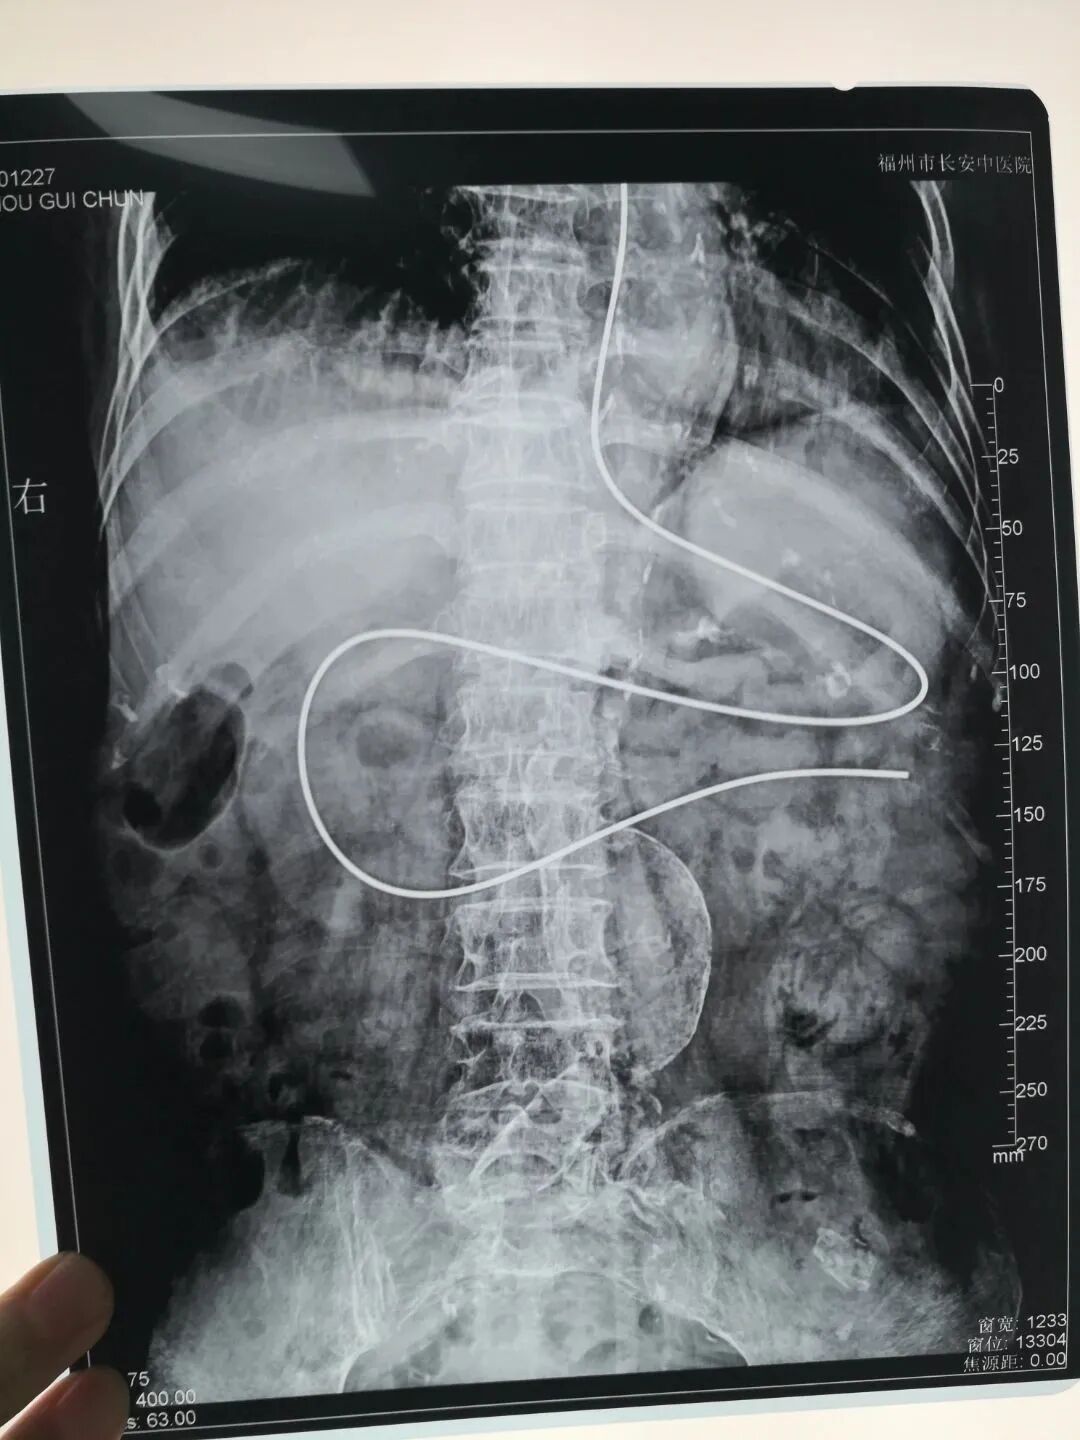

经鼻空肠管置管术是指将空肠管由鼻腔经食管插入小肠,成人一般插入深度为95-105cm。通过空肠管供给食物和药物,不仅能满足病人对营养和治疗的需要,还能防止食物反流、误吸。

应用饲管定位系统辅助下经鼻空肠管置管术,可实现可视化饲管,能准确追踪导丝尖端传感器的相对位置和轨迹;同样的,在使用过程中需判定患者置管位置时,重新嵌入带有传感器的导丝时,系统即可提供可视化轨迹,从而准确检查鼻肠管持续放置的正确位置,该过程还能减少患者接触不必要的X射线辐射和更换鼻肠管的风险。

4、几乎消除了使用X射线确定位置的需要,减少患者不必要的有害辐射;